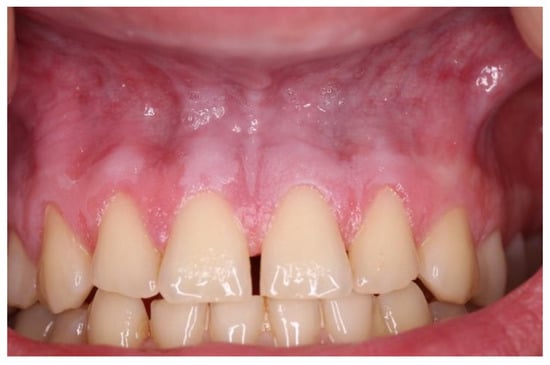

| Snus | 5–10 | 2–5 | White, grainy lesion (Figure 3) | Above tooth nr. 13/12 and 22/23 |